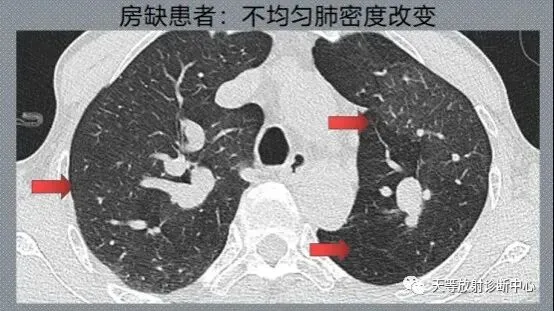

图3,房缺患者,肺动脉高压导致马赛克灌注。

(2)肺动脉高压:胸部CT可见肺实质内马赛克征,高密度区血管增粗,低密度区血管纤细,小叶间隔增厚。也可呈斑片状影、肺小结节影。肺动脉干直径大于29mm预测肺动脉高压的敏感性为87%,但肺动脉干大小正常不能排除肺动脉高压。如果肺动脉干与升主动脉直径比值>1,肺动脉高压的可能性非常高。大多数肺动脉高压病例表现为外周血管修剪,但偶尔也可见外周肺动脉扩张。三个或更多肺叶的段动脉/支气管直径比值大于1:1对肺动脉高压更具特异性。